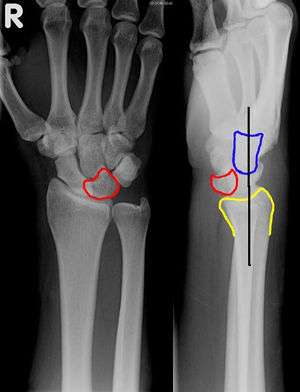

Lunate Dislocation

Lunate Dislocation

- Lateral view

- Lunate is pushed off the radius into the palm ("spilled teacup" sign)

- PA view

- Lunate has triangular shape ("piece-of-pie sign")